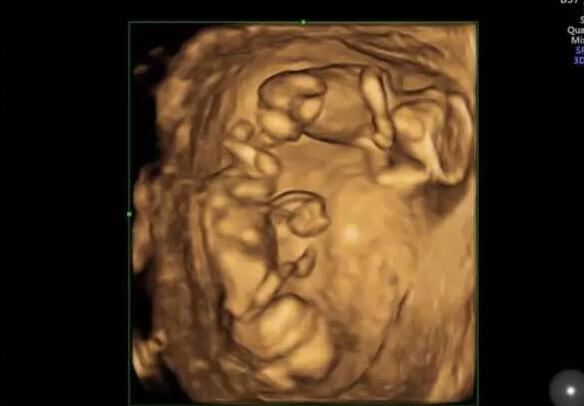

重庆试管供卵 重庆三代试管包生男孩多少费用?生男孩费用十万够吗? ‘三维男

亳州试管婴儿医院排名,附成功率及费用介绍 ‘三维宝宝面